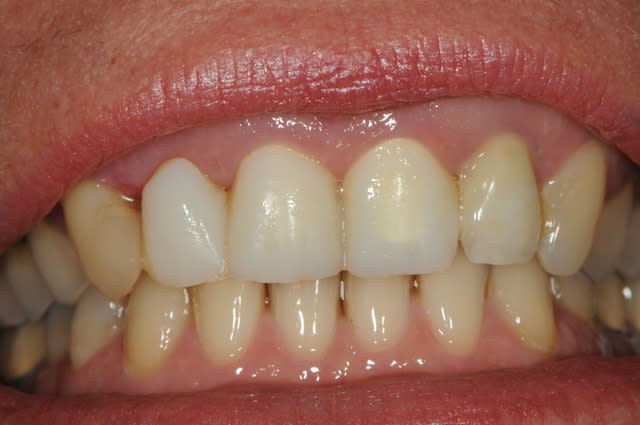

voici - voilà:

photo

1: j+ 2 ou 3 jours

2: j+8 mois

3-4-5: j+ 2 ans

sur la photo 3 on voit à la gencive que l'aspect est moins granité au niveau du col.

c'était ça l'indice pour trouver Charlie.